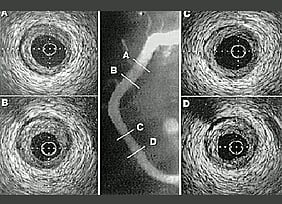

Intra Vascular Ultrasound (IVUS)

Optical Coherence Tomography (OCT)

This is similar to IVUS but uses light instead of ultrasound to achieve its images. it is a new technique which is being increasingly used as its pictures are far more detailed than those achieved with IVUS. As with IVUS it provides information regarding shape and size of arteries but also amount and type of fat build up.